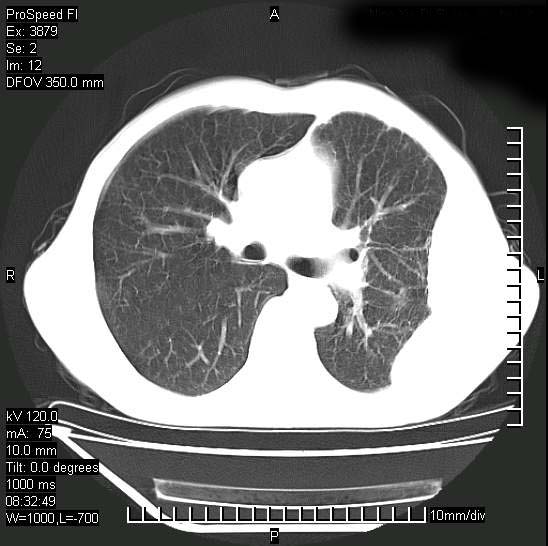

以下是引用37度在2008-6-6 11:20:00的发言:[br]1.包裹性积液,多考虑结核性;[br]2.穿刺术后改变。

以下是引用312nanyang在2008-6-6 15:12:00的发言:[br]基本支持楼主意见[br]疑问?左下肺支气管旁的软组织(16层)密度怎么解释?淋巴结还是斜裂胸膜增厚所致?能否增强进一步检查